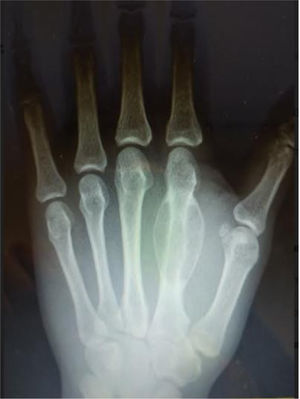

Varón de 40 años de edad, inmigrante de origen pakistaní, que consultó en Atención Primaria por tumoración dolorosa en el dorso de la mano izquierda de aproximadamente un mes de evolución que –por su localización y consistencia– nos pareció inicialmente un ganglión sinovial, aunque por su actividad laboral en la construcción tampoco se podía excluir un traumatismo previo (barrera idiomática importante). Para descartar un callo óseo por fractura subyacente se solicitó radiografía simple de la mano que mostró una inesperada lesión osteolítica en la diáfisis del 2.° metacarpiano, con reacción perióstica longitudinal (fig. 1). Por persistencia del dolor se instauró pauta oral de antiinflamatorios no esteroideos con mejoría sintomática, derivándose a Traumatología para agilizar las pruebas de imagen y pensando ya en un abordaje quirúrgico de la lesión. En la resonancia de la mano (fig. 2) se visualizó una tumoración en la cara dorsal de la diáfisis del 2.° metacarpiano, heterogénea y de crecimiento expansivo, con unas medidas de 32x20x13mm. Tras valoración por el Comité de Tumores del aparato locomotor se decidió biopsia ósea guiada por tomografía computarizada, con diagnóstico histológico de: tumor de células gigantes de huesos pequeños. Fue intervenido mediante exéresis radical y autoinjerto de cresta cubital, con buena evolución y sin secuelas motoras ni sensitivas. Después de cuatro años de seguimiento, el paciente está asintomático y sin recidivas locales ni sistémicas.

Imagen de RX simple: lesión lítica expansiva –de origen intramedular y que se extiende excéntricamente– en la región dorsal de la diáfisis del 2.° metacarpiano, rodeada de un arco arbotante de reacción perióstica en sus extremos proximal y distal. Según el radiólogo, en el diagnóstico diferencial se incluirían tres entidades: quiste óseo aneurismático, fibroma condromixoide y tumor de células gigantes, recomendando ampliar el estudio mediante resonancia magnética (RM).